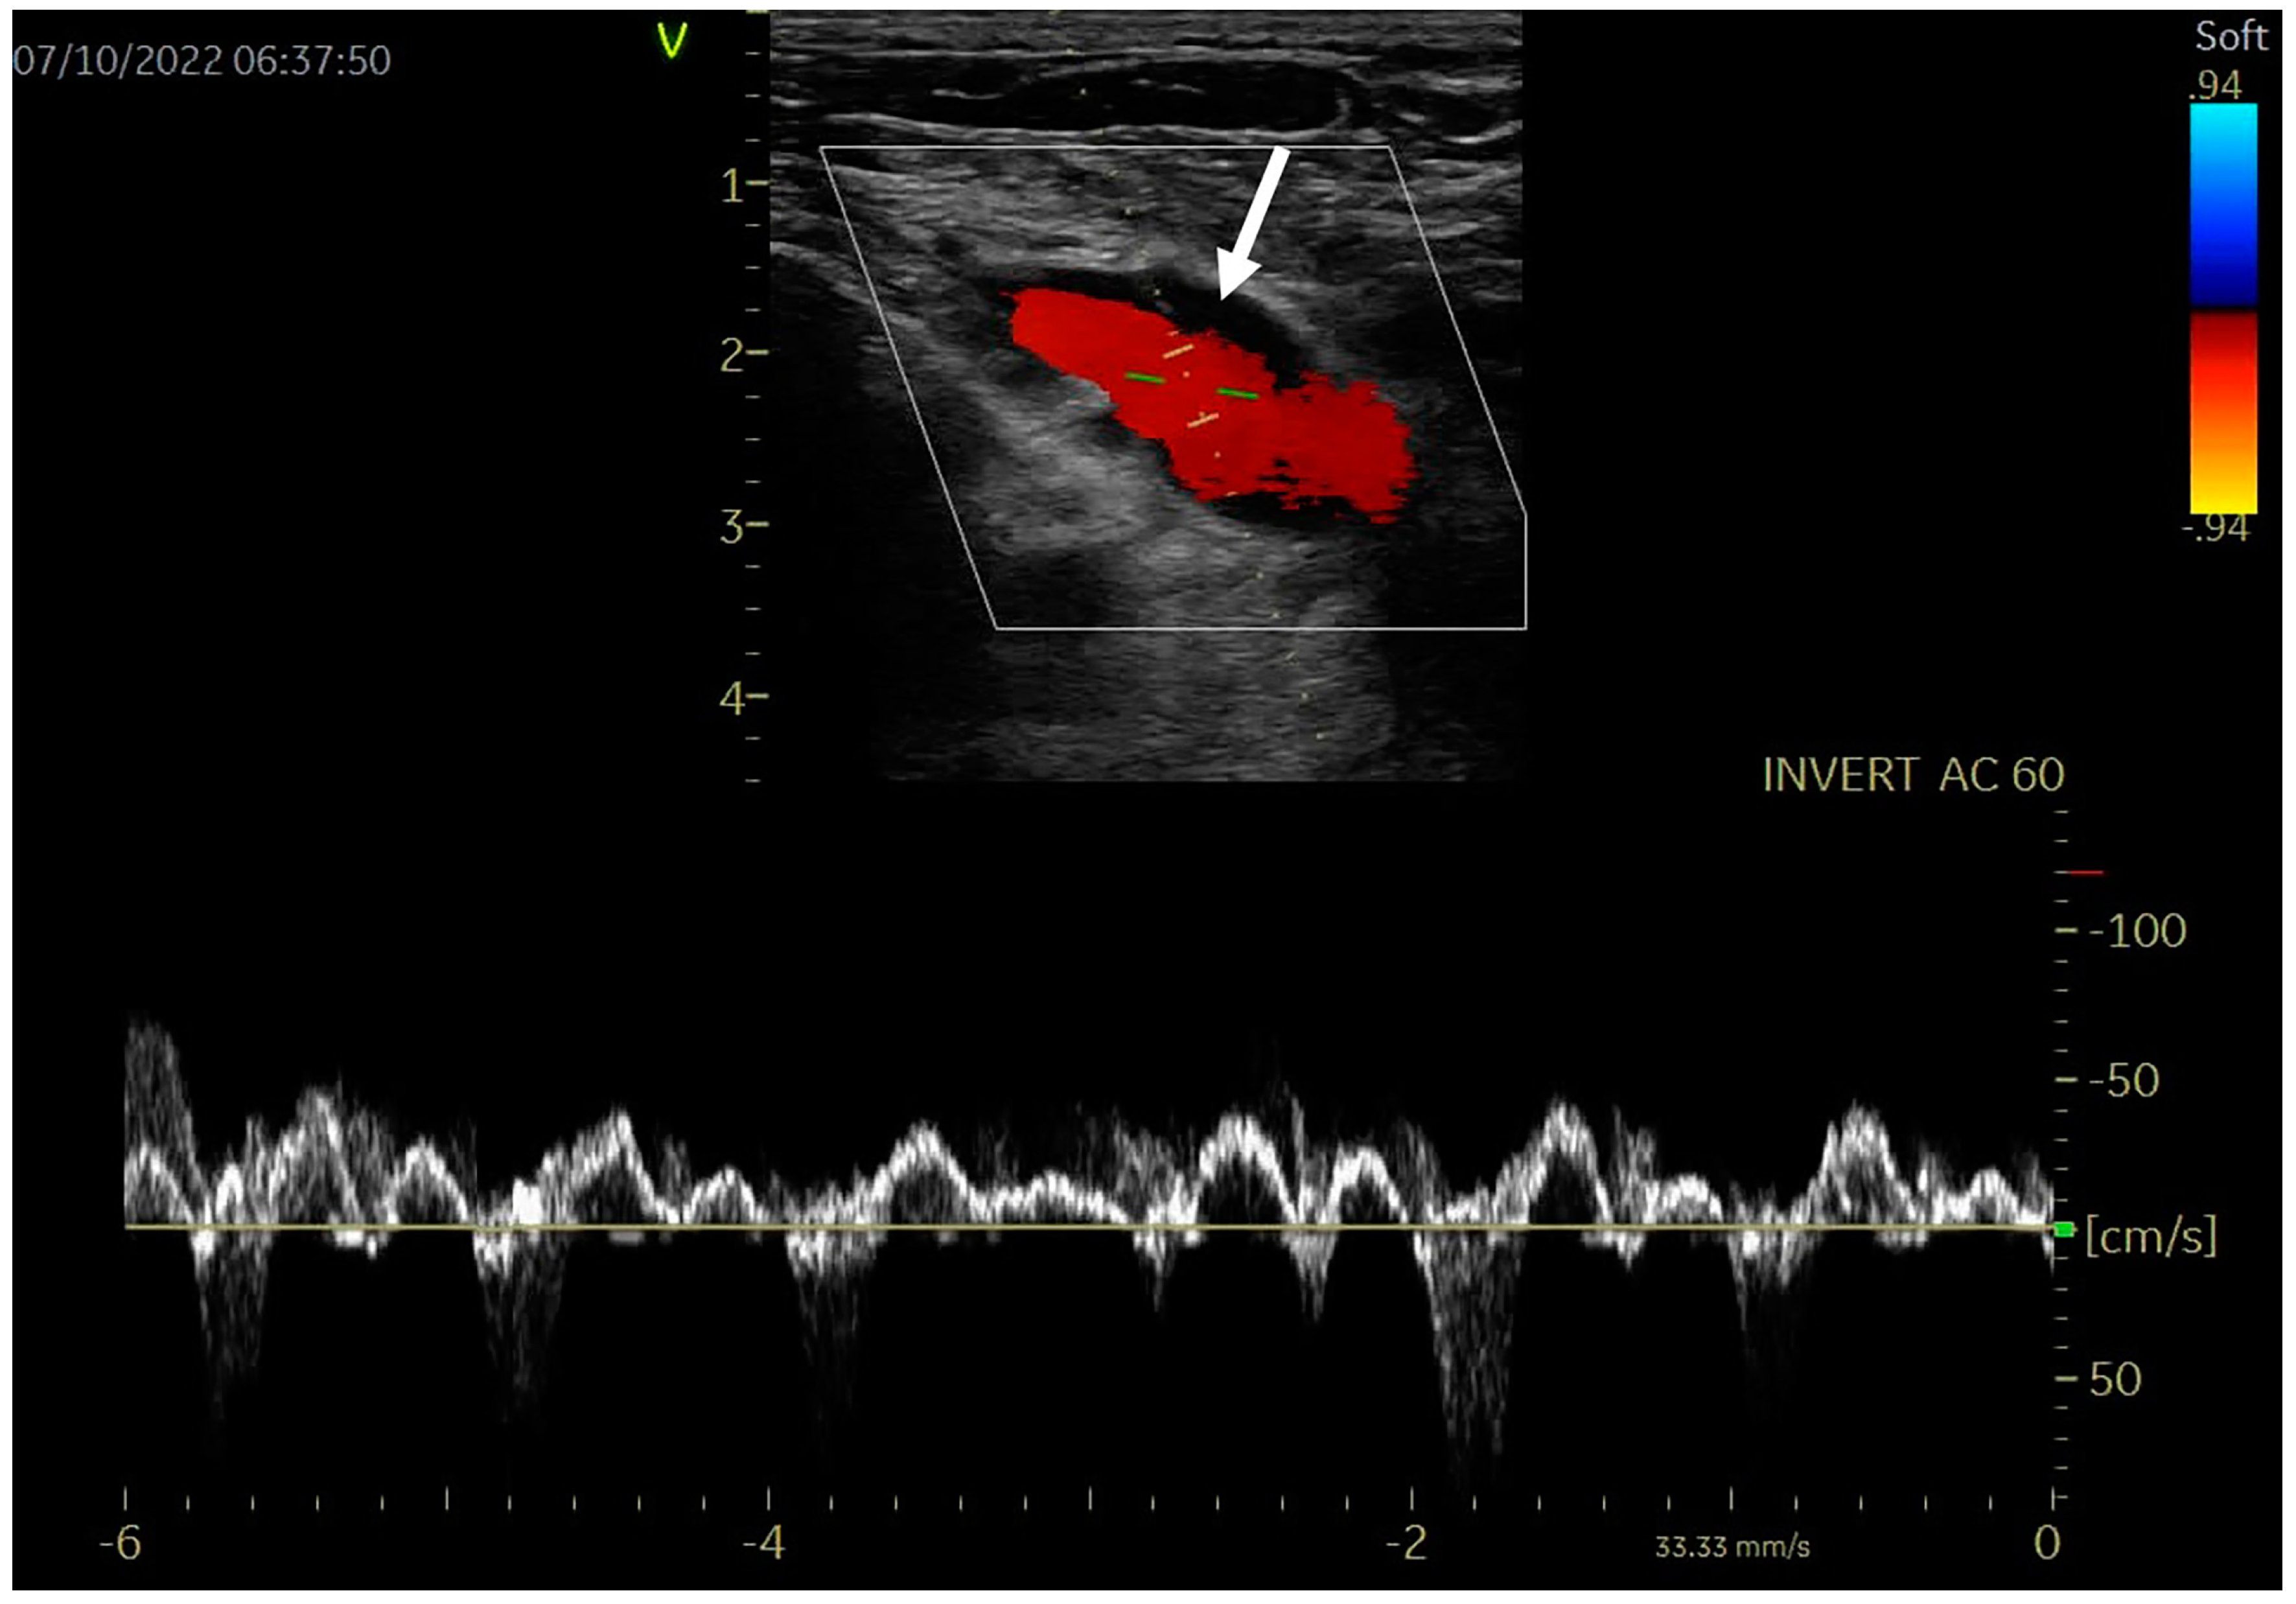

After three months of oral anticoagulation, thoracic outlet decompression with first rib resection through a trans-axillary approach was performed successfully. Oral anticoagulation was continued for another 3 months after surgery and the patient became asymptomatic. During ultrasound reevaluation, the patency of the veins was complete, without thrombus, spontaneous contrast, venous stenosis or recurrent DVT, as shown in Figure 3. Shortly after surgical decompression, the patient resumed his professional activity. At the 6- and 12-month follow-up, the clinical examination and venous ultrasound were normal.

Figure 3. Venous ultrasound: left subclavian vein recanalization (white arrow), with normal color Doppler (red content) and pulsed Doppler flow.